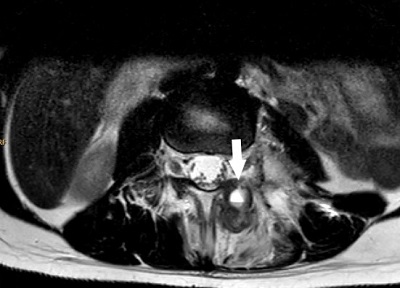

Ante una dorsalgia con datos de alarma (afectación neurológica) se realiza radiografía de columna vertebral (Fig. 1) que muestra una lesión lítica, expansiva, en pedículo derecho a nivel T10 y resonancia magnética (RM) de columna vertebral donde se aprecia una masa lobulada insuflante con cortical conservada pero adelgazada y nivel líquido en su interior en elementos posteriores de T10 que se introduce hacia el cuerpo vertebral, con componente epidural derecho que ocupa el 50-75% del canal medular y compresión medular con alteración de señal por mielopatía (desde nivel T8-T9 hasta cono medular), planteando el diagnóstico diferencial con lesiones tumorales de localización vertebral posterior, como son el osteoblastoma y el quiste óseo aneurismático (Fig. 2).

| Figura 2. RM de columna vertebral: masa lobulada insuflante en elementos posteriores de T10 que se introduce anteriormente hacia el cuerpo vertebral, rodeada de cortical ósea marcadamente adelgazada con múltiples niveles líquido-líquido junto con alteración de la señal de la musculatura paravertebral derecha por edema asociado (flechas). Asocia componente epidural en canal medular con compresión medular, ocupando el 50-75% de su totalidad |